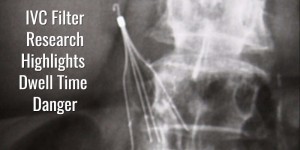

IVC Filter Retrieval: A Longer Dwell Time Means More Risk